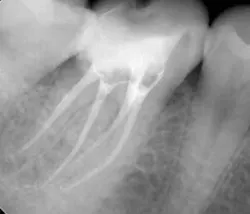

Step 3: Obturate

Canals are carefully dried with paper points. Insert the gutta-percha with AH sealer in the canal to working length, and take it back out. Add additional sealer to the gutta-percha, and then in a gentle pumping motion insert gutta-percha back to working length. Sear off access with a thermal pen and apply gentle pressure with a condenser.

Using a pumping motion and adding additional sealer ensures that voids within the canals get filled. This generates the “puff” effect with small amount of sealer being extruded from the apex of canals. It also helps ensure accessory canals are not left unfilled.